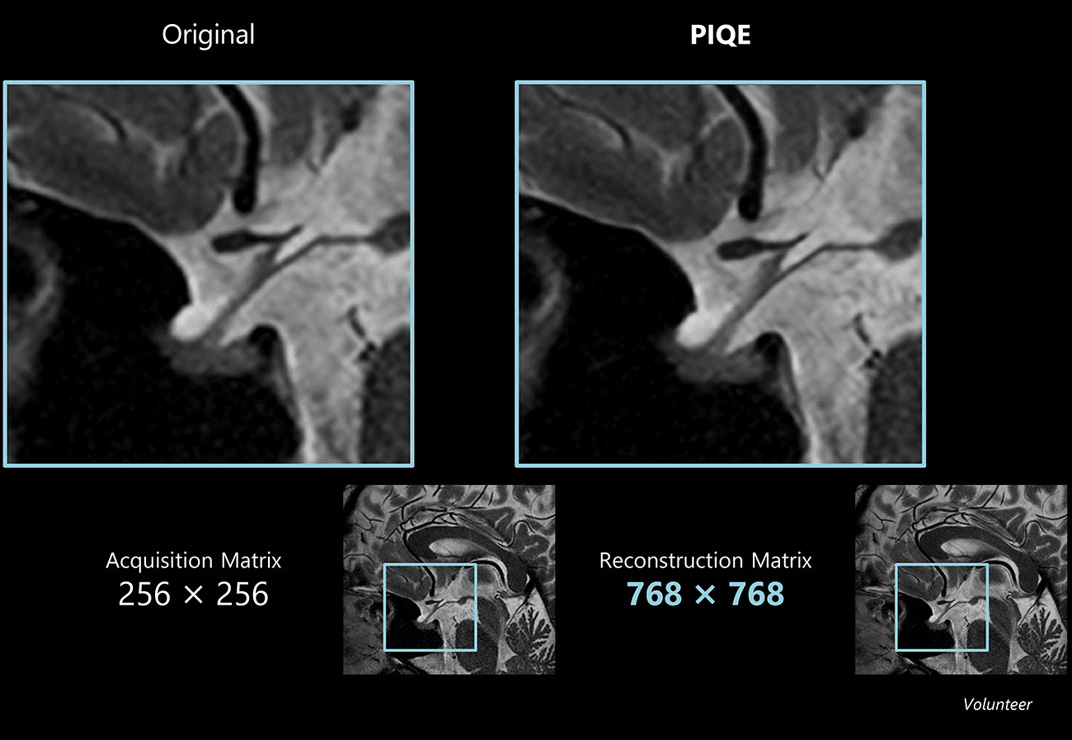

Sag T2w for pituitary

Using a regular head and neck coil, with a collection matrix 256 × 256 setting, imaging can be performed in approximately 1 minute. Structures around the pituitary gland are clearly visible.

Acquisition time: 1:08